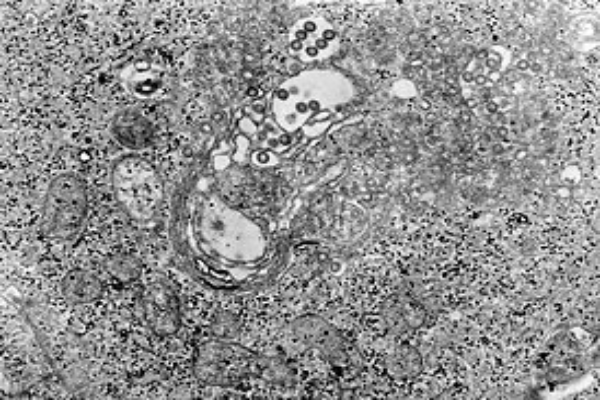

Вирусы-возбудители лихорадки Рифт-Валли относятся к семейству Phenuiviridae рода Phlebovirus вида Rift Valley fever phlebovirus. Это мелкий РНК-содержащий вирус. Размер вирионов 60-75 нм. Установлено различие в размерах вирионов, отличающихся по тропизму.